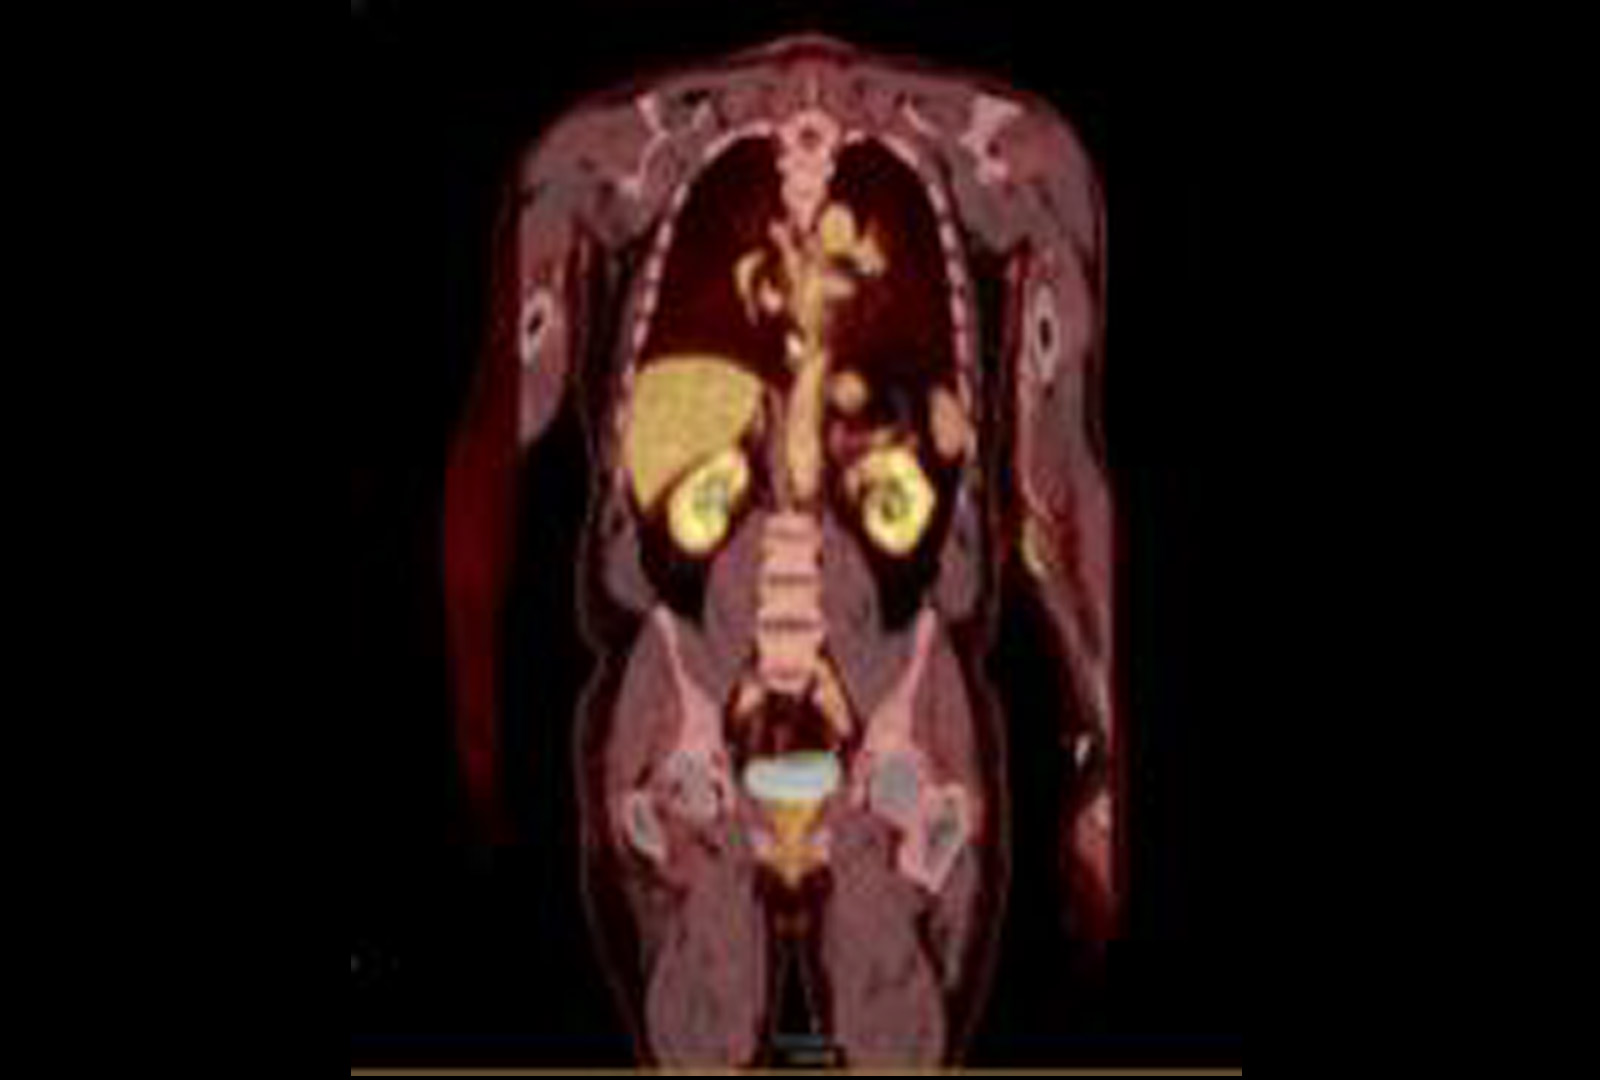

FDG Uptake

PET/CT showing FDG uptake at the distal esophagus, consistent with malignancy. There is also FDG uptake at the gastroesophageal junction, likely inflammatory or physiologic, along with FDG-avid bilateral hilar foci, right axillary nodes, and a right inguinal node—findings most consistent with inflammation. Source: NYU Langone Health